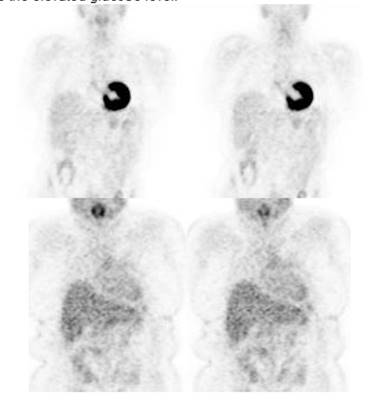

Figure 4 - Myocardial activity: Myocardial uptake can be

very variable. The patient on the left below had a glucose level of 97 prior to

FDG injection. Despite the normal serum glucose, note the intense cardiac

activity in this patient. The patient on the right